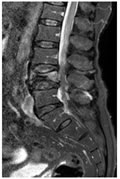

CASE 7

STIR SAGITTAL IMAGE SHOWING WEDGE SHAPE COLLAPSE OF L3 VERTEBRAL BODY WITH HYPERINTENSE SIGNAL WIHTIN

T1W AXIAL IMAGE SHOWING SEVERE THECAL SAC STENOSIS DUE TO DIFFUSE DISC BULGE AT L3-L4 LEVEL

POST CONTRAST T1W IMAGES SHOWING ENHANCEMENT OF THE L3 VERTEBRAL BODY, DURAL ENHANCEMENT FROM L3 TO L4 LEVELS AND POSTERIOR ELEMENT ENHANCEMENT LIKELY TO BE INFECTIVE / NEOPLASTIC ETIOLOGY.